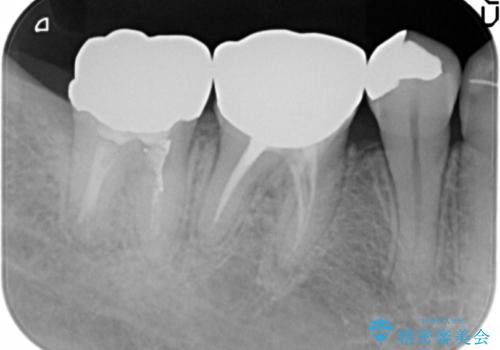

右上小臼歯(右上5)はオールセラミッククラウン(e-max press)、下顎臼歯(下顎両側67)はメタルボンドクラウンによりやりかえることにしました。

再根管治療はご希望されず、行っておりません。